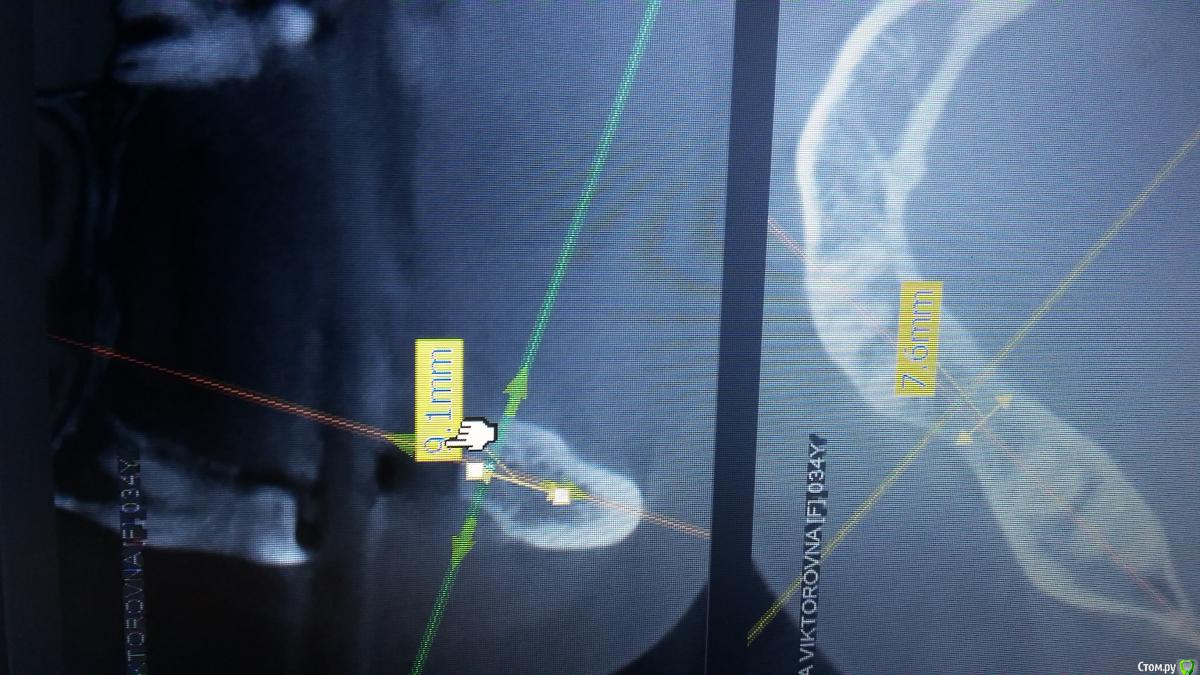

Антон 123 Опубликовано 14 февраля, 2019 Поделиться Опубликовано 14 февраля, 2019 (изменено) Всем форумчанам доброго времени суток. Ставлю импланты недавно,поэтому хочется спросить мнение более опытных коллег. Условия для имплантации следующие зуб 46, до канала9 мм, гребень 7,6мм,угол примерно 20 градусов. Выбрал имплант диаметр 4.5 мм - 8.5 мм длина . Остальные все зубы у пациента есть. Кто что думает? Изменено 14 февраля, 2019 пользователем Антон 123 Ссылка на комментарий

Irouil Опубликовано 14 февраля, 2019 Поделиться Опубликовано 14 февраля, 2019 (изменено) Своеобразно Вы ширину гребня измеряете... 4.5*7, но я бы перезамерил Изменено 14 февраля, 2019 пользователем Irouil Ссылка на комментарий

red_butler Опубликовано 14 февраля, 2019 Поделиться Опубликовано 14 февраля, 2019 а в чем ошибку заметили?я открыт для критики,так как опыта мало,лучше я здесь о своих касяках узнаю,чем в момент имплантации)))мне видится высота 10-10,5 мм, голосую за имплант длиной 7 мм Ссылка на комментарий

Тимур86 Опубликовано 15 февраля, 2019 Поделиться Опубликовано 15 февраля, 2019 (изменено) Мне тоже кажется ~10.5, я бы взял 8.5 Изменено 15 февраля, 2019 пользователем Тимур86 Ссылка на комментарий

Irouil Опубликовано 15 февраля, 2019 Поделиться Опубликовано 15 февраля, 2019 а в чем ошибку заметили?я открыт для критики,так как опыта мало,лучше я здесь о своих касяках узнаю,чем в момент имплантации)))Наискосок как-то, ширина получается больше, длинна - меньше Можно пробовать сверлиться на 8.5, но конус же, будете глубить 1-1.5 мм, вплотную к каналу. В случае не дай бог каких разбирательств шансы оказаться крайним выше Судя по объёмам альвеолярного гребня челюсти у пациента небольшие, нагрузки тоже пропорционально, семёрка должна работать нормально Ссылка на комментарий